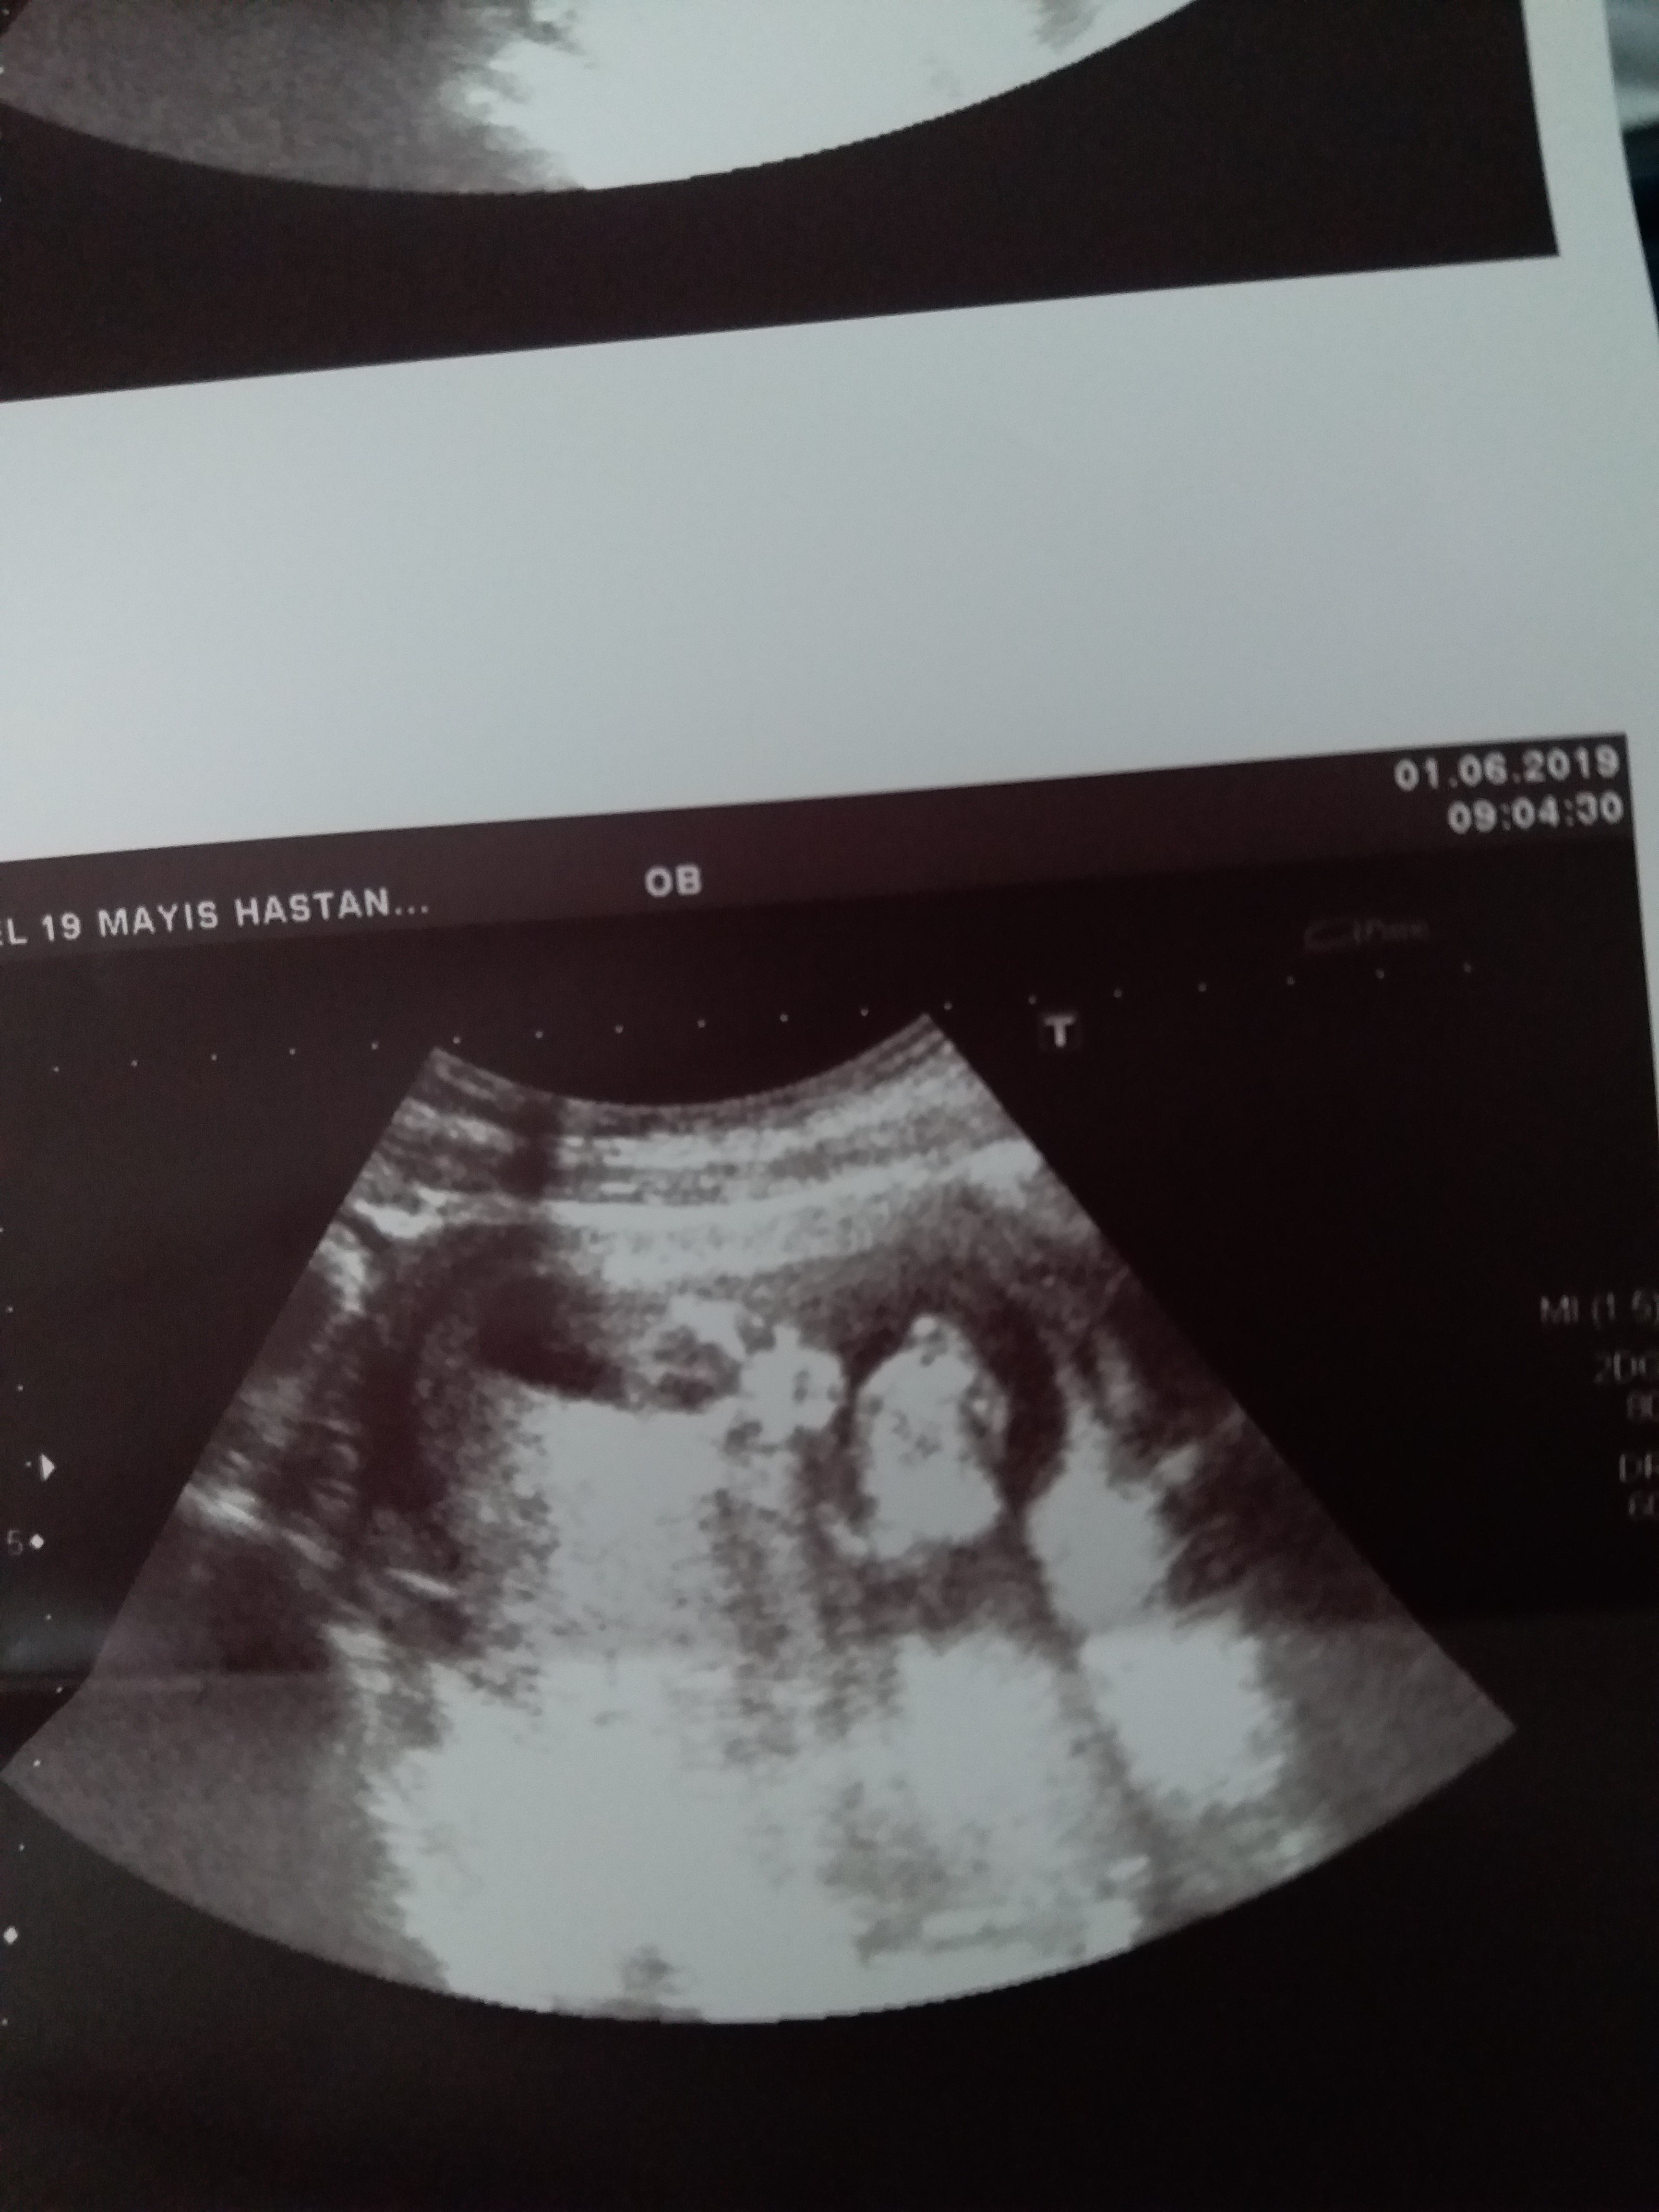

Nub cinsiyet tahmini tutanlar beni de değerlendirir misiniz lütfen ?

Sizce cinsiyet nedir ya bu hafta tekrar gittim doktora net konuşmadı 12 haftadayız lütfen bilen Allah rızası için yardımcı olsun